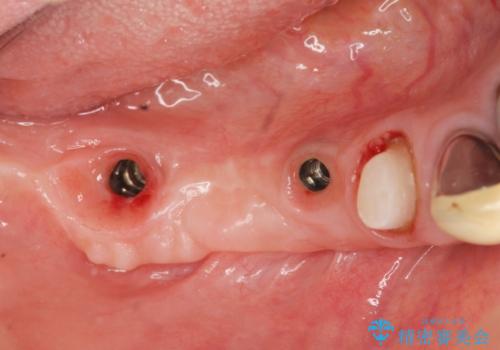

狭小な歯槽骨に対するインプラント治療

- 歯を失い噛めないこと、骨の幅が狭く他院でインプラント治療が難しいと断られ、当院でのインプラント治療が可能かどうか相談来院されました。

骨の造成、角化歯肉の移植を行いインプラント周囲の環境を整えた治療を計画します。

遊離歯肉移植術(硬い歯ぐきのインプラント周囲への移植)を行ったことで、炎症に強く歯ブラシのしやすい環境をインプラント周囲に整えることができました。